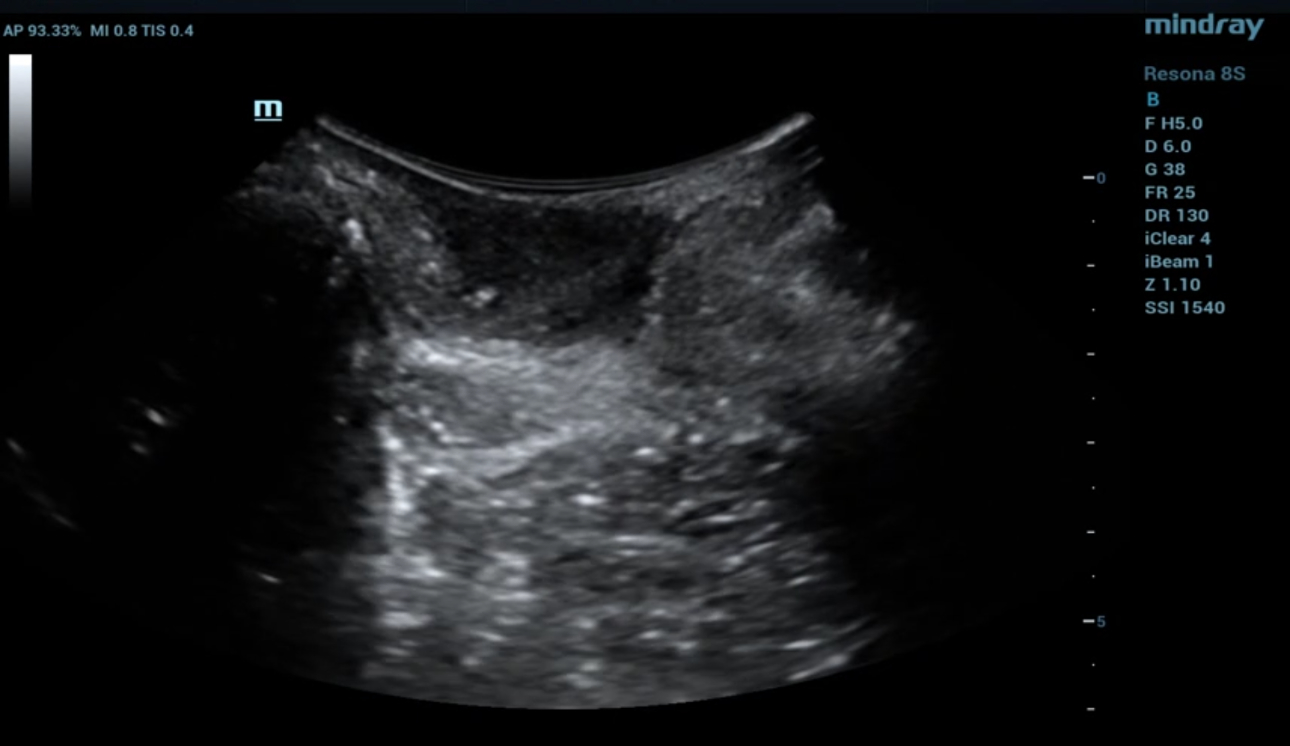

levator-trauma-fig6-pc

형상 4. 좌측 avulsion의 Ipage+ 이미지